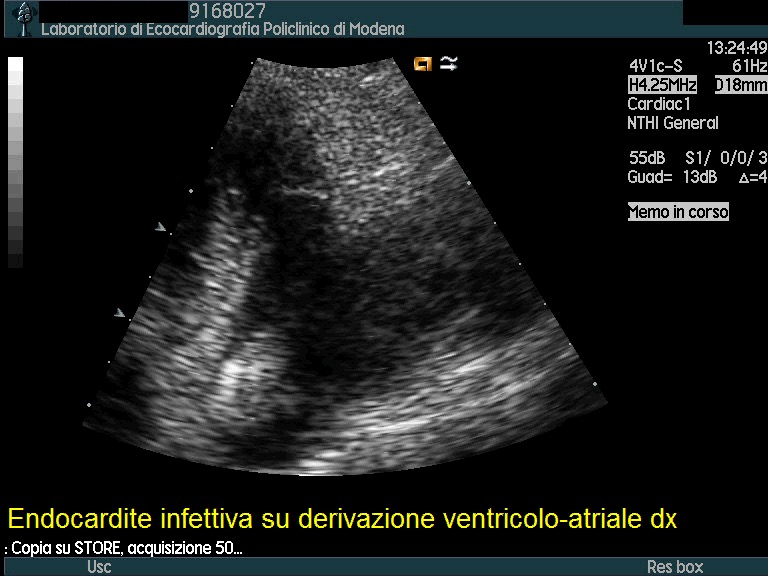

Titolo:

Endocardite su derivazione ventricolo-atriale destra

Autore:

Andrea Barbieri